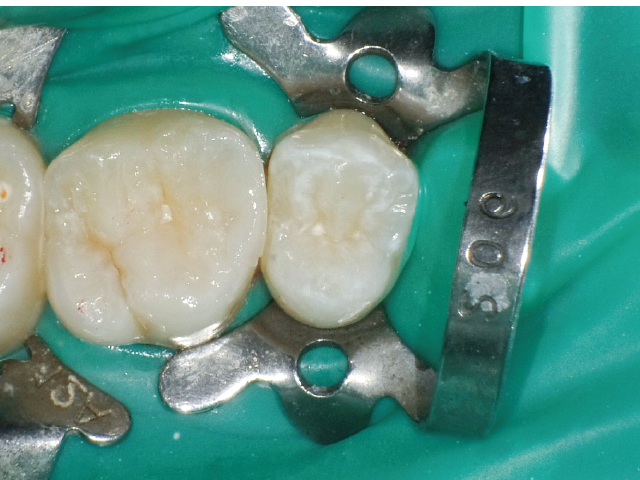

②充填段階(図10~22)

窩洞形成完了後は隣接面部健全歯質の残存範囲によりコンポジットレジンの充填時に用いるマトリックスシステムを選択していきますが、今回はシンプルな操作で設置可能なトッフルマイヤータイプのマトリックスシステムを選びました。隣在歯との距離が小さく、フラットな隣接面形態の再現が必要な症例には最適で、同時に精度の高い窩洞の防湿も可能です。使用したメタルのマトリックスバンドの厚さは30µmと非常に薄く、隣在歯との間に適切な接触関係を回復することができます。

接着操作には窩縁部エナメル質へのセレクティブエッチングに続いて、2ステップタイプのセルフエッチングシステム(クリアフィル® メガボンド®2 : クラレノリタケデンタル)を使用し、フロアブルレジンとペーストタイプレジンとを併用したシンプルな積層充填操作により隣接面形態を回復しました。